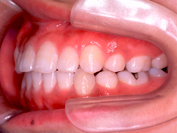

叢生 治療後

歯を抜いたスペースを利用して、残りの歯をきれいに並べ替えてゆきます。この患者さんの場合は、抜いたスペースはほとんど余りませんので、意外に早く治療が終わりました。